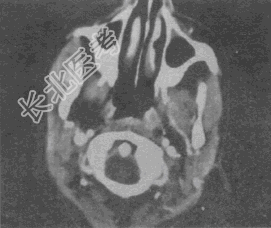

- 单项选择题女,16岁, 右侧面颊部肿胀,CT扫描如图所示, 最可能的诊断是

A、右侧咬肌区血管瘤

B、右侧咬肌区脂肪瘤

C、右侧咬肌区皮样囊肿

D、右侧咬肌区淋巴管瘤

E、右侧咬肌区慢性淋巴管炎